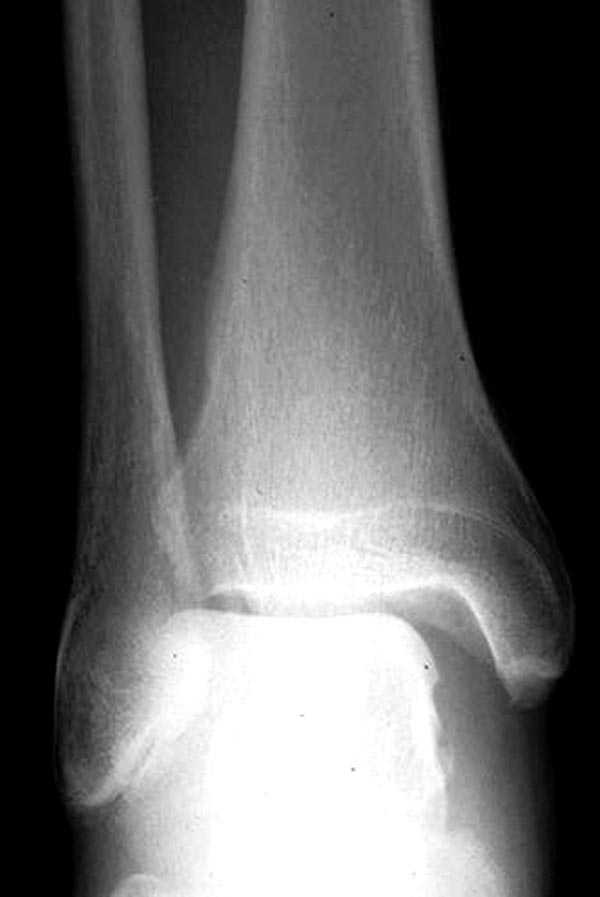

Здесь как раз тот случай, когда рентгеновский снимок скрывает главную проблему. "Ходит, прихрамывая на правую ногу, отмечает боли в правом голеностопном суставе" По описанию клиника типичная для повреждения голонестопного сустава - синдесмоза.

Для уточнения диагноза надо сделать все стандартные снимки голеностопа, (несмотря на необходимость при любых повреждениях голеностопа, почему-то очень трудно воспроизводится коллегами из СНГ?)

На прямой проекции можно увидеть расширенную медиальную щель, и на мортизе укорочение малоберцовой.